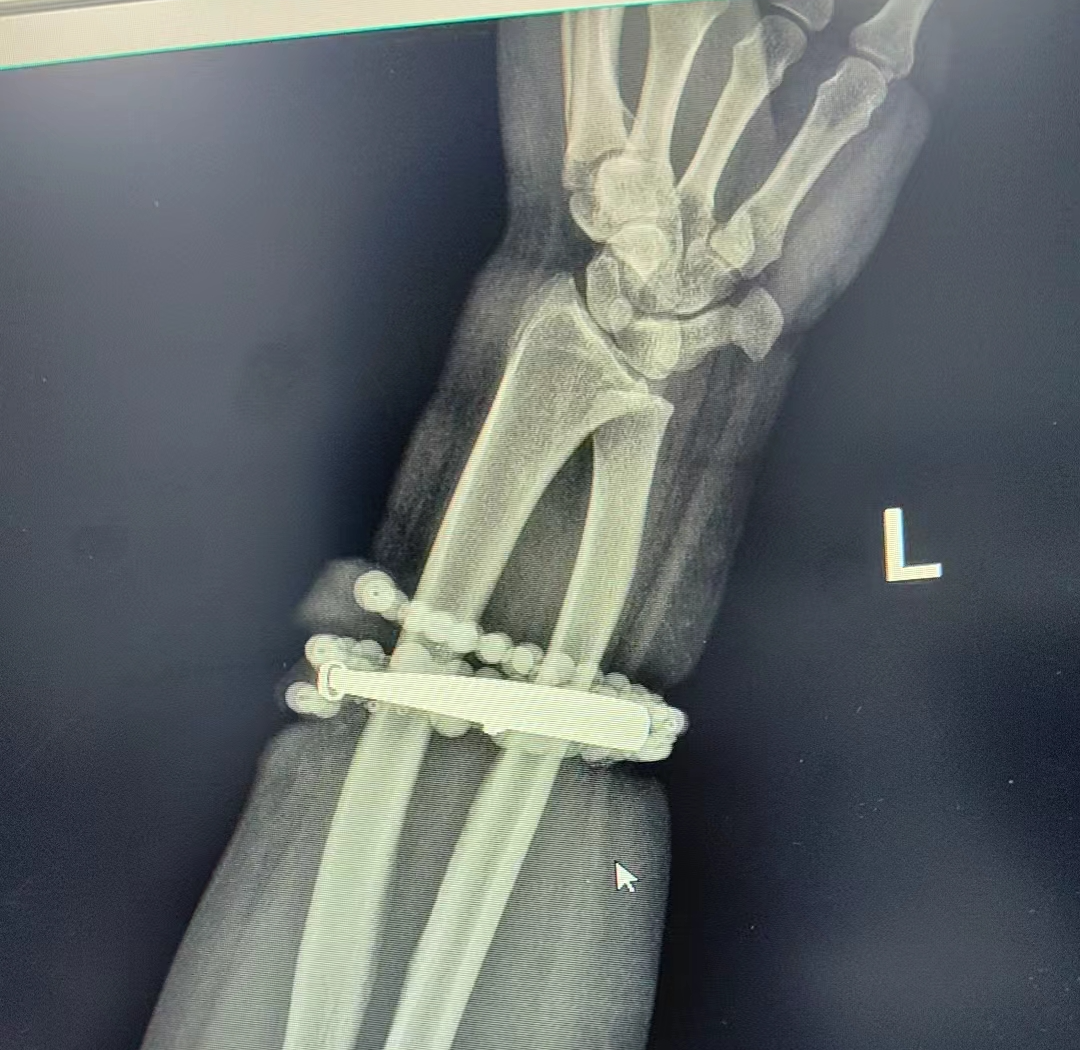

戴了十年没摘的手镯、串珠竟长进了肉里,还发炎了!近日,福建省宁德市闽东医院创伤骨科、手显微外科就接诊了这样一位患者。

然而,就在两周前,龚女士的情况急转直下:手腕不仅疼痛加剧,还出现了明显的红肿,甚至有脓液渗出。她这才惊觉——手镯和串珠,已经有一部分“长”进了肉里,根本取不下来了!

“这是典型的首饰长期压迫、摩擦,加上细菌感染,引发的慢性炎症和肉芽组织增生。”医生介绍,此时,手镯和串珠已经成了一个不断刺激皮肤、污染伤口的“病灶”,如果不尽快手术取出,感染可能进一步扩散,甚至危及生命或影响手臂功能。

经过一个多小时的手术,医生们将手镯和串珠从厚厚的增生组织中完整剥离出来。目前,龚女士恢复良好,已顺利出院。